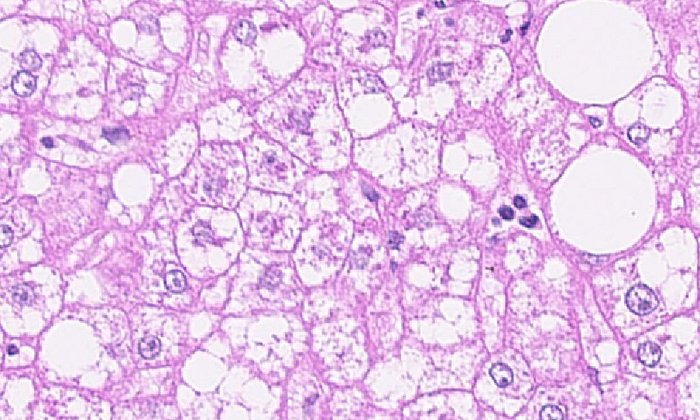

In ihrer neuen Studie, die jetzt in „Nature“ veröffentlicht wurde, gelang den Wissenschaftlerinnen und Wissenschaftlern ein wichtiger Schritt: Sie konnten zeigen, dass auch die fehlerhaften T-Zellen einen Not-Ausschalter, einen so genannten Tumorsuppressor haben. Sie fanden heraus, dass das Protein PD-1 defekte T-Zellen frühzeitig abschalten kann und so verhindert, dass sie zu Tumorzellen werden. Die Forscherinnen und Forscher entdeckten diese Funktion von PD-1 zuerst in einem Mausmodell für T-Zell-Non-Hodgkin-Lymphome und konnten auch den Mechanismus aufklären: PD-1 wird durch Fehler in Genen für das Zellwachstum, so genannten Onkogenen, aktiviert und unterdrückt dann die Wirkung dieser Gene mit Hilfe zusätzlicher Proteine. Es verhindert so als Schutzschalter ein unkontrolliertes Wachstum der defekten T-Zelle.